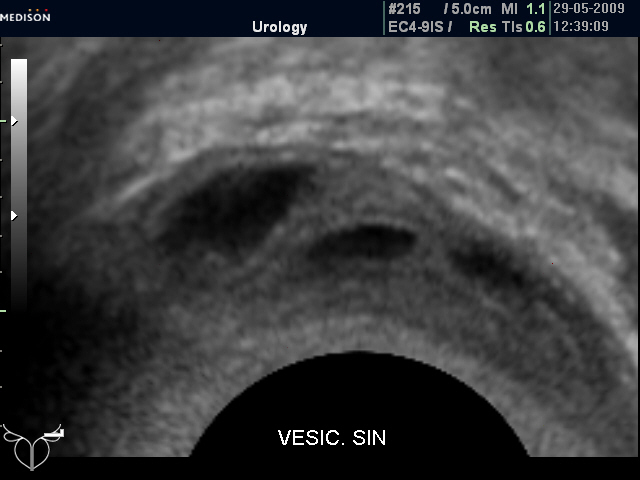

Нормальные семенные пузырьки при ТА и ТР УЗИ (фото 1 и 2).

Нормальные СП (ТР УЗИ)